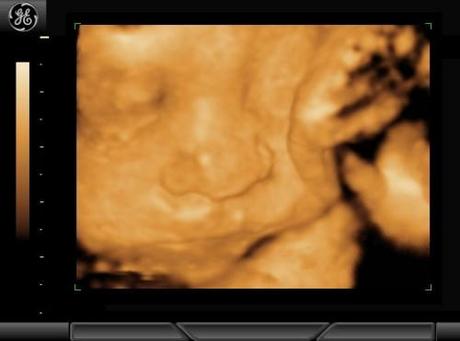

Las ecografías 4D son la última novedad. A partir de decenas de imágenes en 3D permite ver el movimiento del feto en tiempo real. El efecto que causa es el de ver al bebé en un video, puedes ver como parpadea, saca la lengua o se chupa un dedo. Además también puedes observar su aspecto, ya que te permite diferenciar las facciones y los rasgos de su carita.

Este tipo de ecografías complementan a las 2D. Con ellas el diagnóstico se perfecciona. Con la ecografía 2D se detectan las anomalías fetales, y con la 4D podemos apreciar con mayor claridad cuáles son esas anomalías, sobre todo si se trata de problemas en la piel o deformidades como labio leporino o paladar hendido.